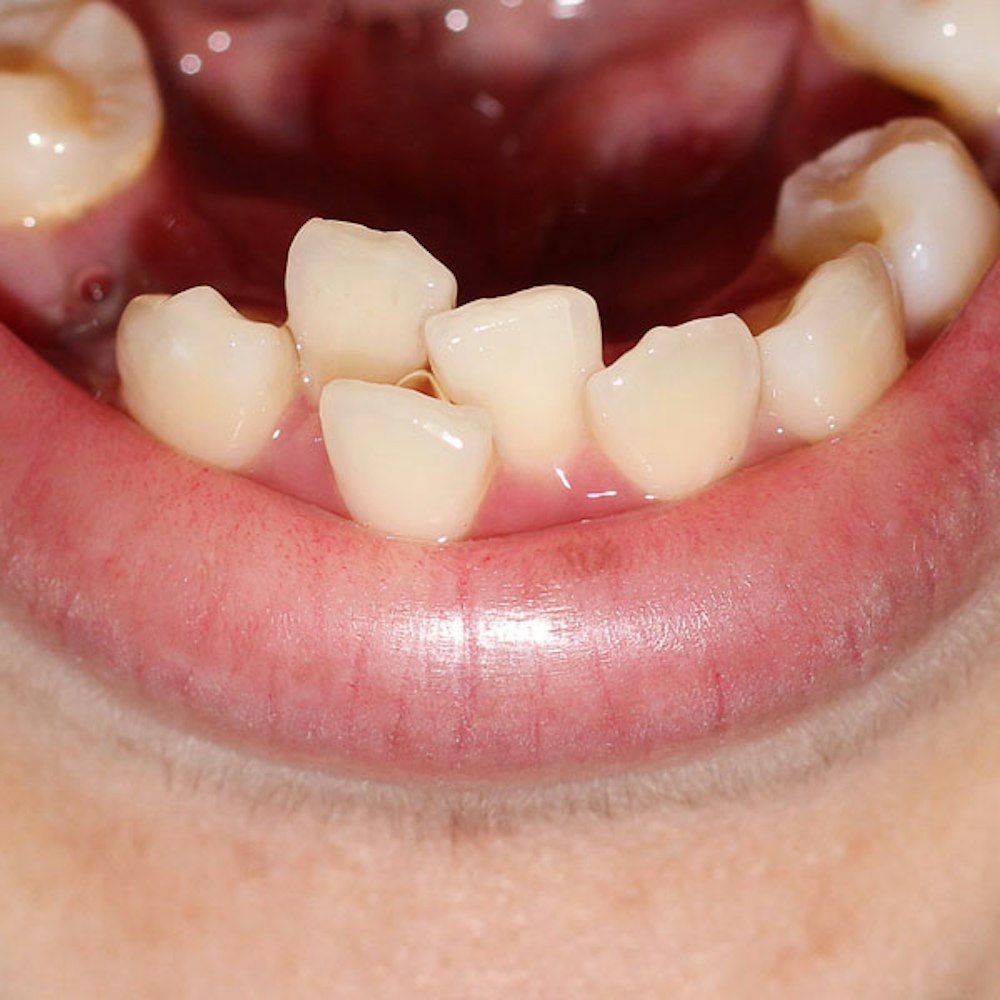

- Relieve Pain: Severely damaged and decaying teeth can cause daily tooth pain. Tooth extractions can give you the freedom to live comfortably and eliminate discomfort.

Take a Closer Look at Tooth Extraction